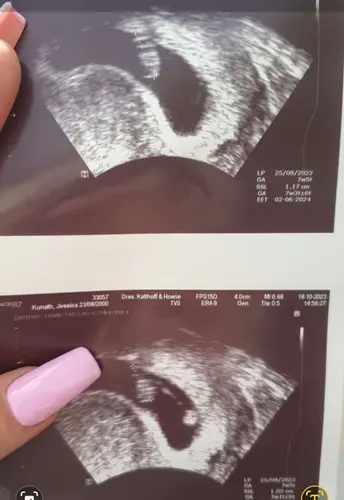

Das Herz sieht man erst ab der 7. Ssw schlagen und bisher sieht der Wert eig. Gut aus

In der letzten ssw hat man ihn bei mir 6+0 gesehen💕

Ah okay 🥰 aber wenn cive s richtig deute bist ja noch in der 6. Ssw bei (5+6 ) kann sein das es dann noch paar tage dauert bei mir hat man es erst in der 6+5 leicht gesehen

Das war bei mir 7+5 im unterem Bild sieht man auch noch den dottersack der sich da schon ändert